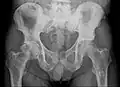

Radio du bassin d'un patient atteint d'un carcinome de la prostate : multiples métastases ostéocondensantes, en particulier sur le sacrum, mais aussi sur l'ilion surtout gauche (à dr. sur l'image), sur la pointe de l'ischion gauche, et sur le fémur proximal gauche. On détecte à l'occasion une arthrose de hanche droite (à g. sur l'image).

Radio du bassin avec métastases ostéolytiques. Les métastases sont sur les deux fémurs et sur le bassin lui-même.